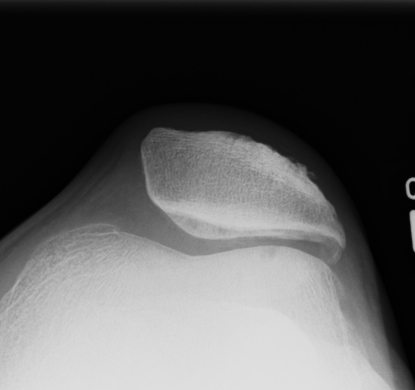

Dejour Crossover Sign

- lateral x-ray at 30o with condyles superimposed

- identify base of trochlea

Normal

- clearly defined trochlea groove